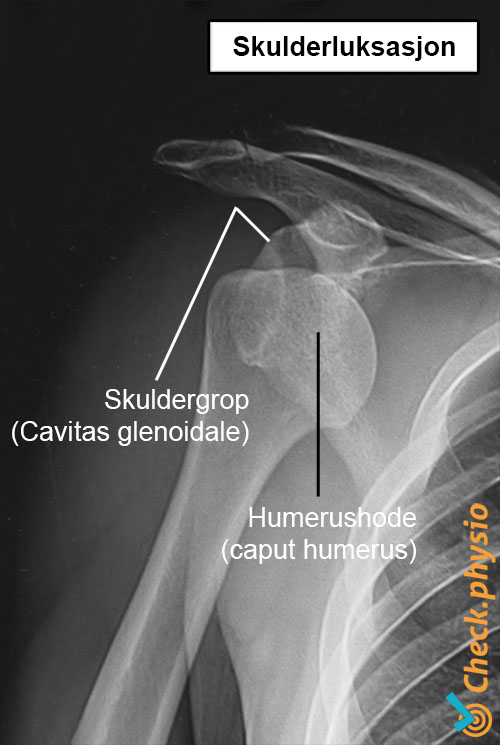

Når en skulderluksasjon oppstår, glir skulderkulen ut av leddpannen, og leddet mister all funksjon. Bånd og leddkapsel kan bli skadet, fordi skulderkulen beveger seg lenger enn disse strukturene tåler.

Ved mistanke om at skulderen er ute av ledd, gjøres videre radiologisk undersøkelse. Et røntgenbilde viser retningen på luksasjonen og om det foreligger et brudd. Det bør også undersøkes om muskler eller leddkapsel er skadet.